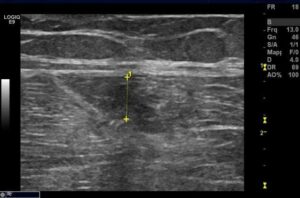

28.12.2010

In corrispondenza del terzo prossimale del muscolo retto femorale di destra si osserva area anecogena a margini netti che misura 44,3 mm. in scansione longitudinale.

Quadro compatibile con versamento, verosimilmente ematico, secondario a trauma contusivo diretto.

11.01.2011

In corrispondenza del terzo prossimale del muscolo retto femorale di destra si osserva completa risoluzione del versamento precedentemente riscontrato.

Si consiglia ripresa sportiva graduale (idrokinesiterapia, esercizi isometrici e poi training concentrico/eccentrico).